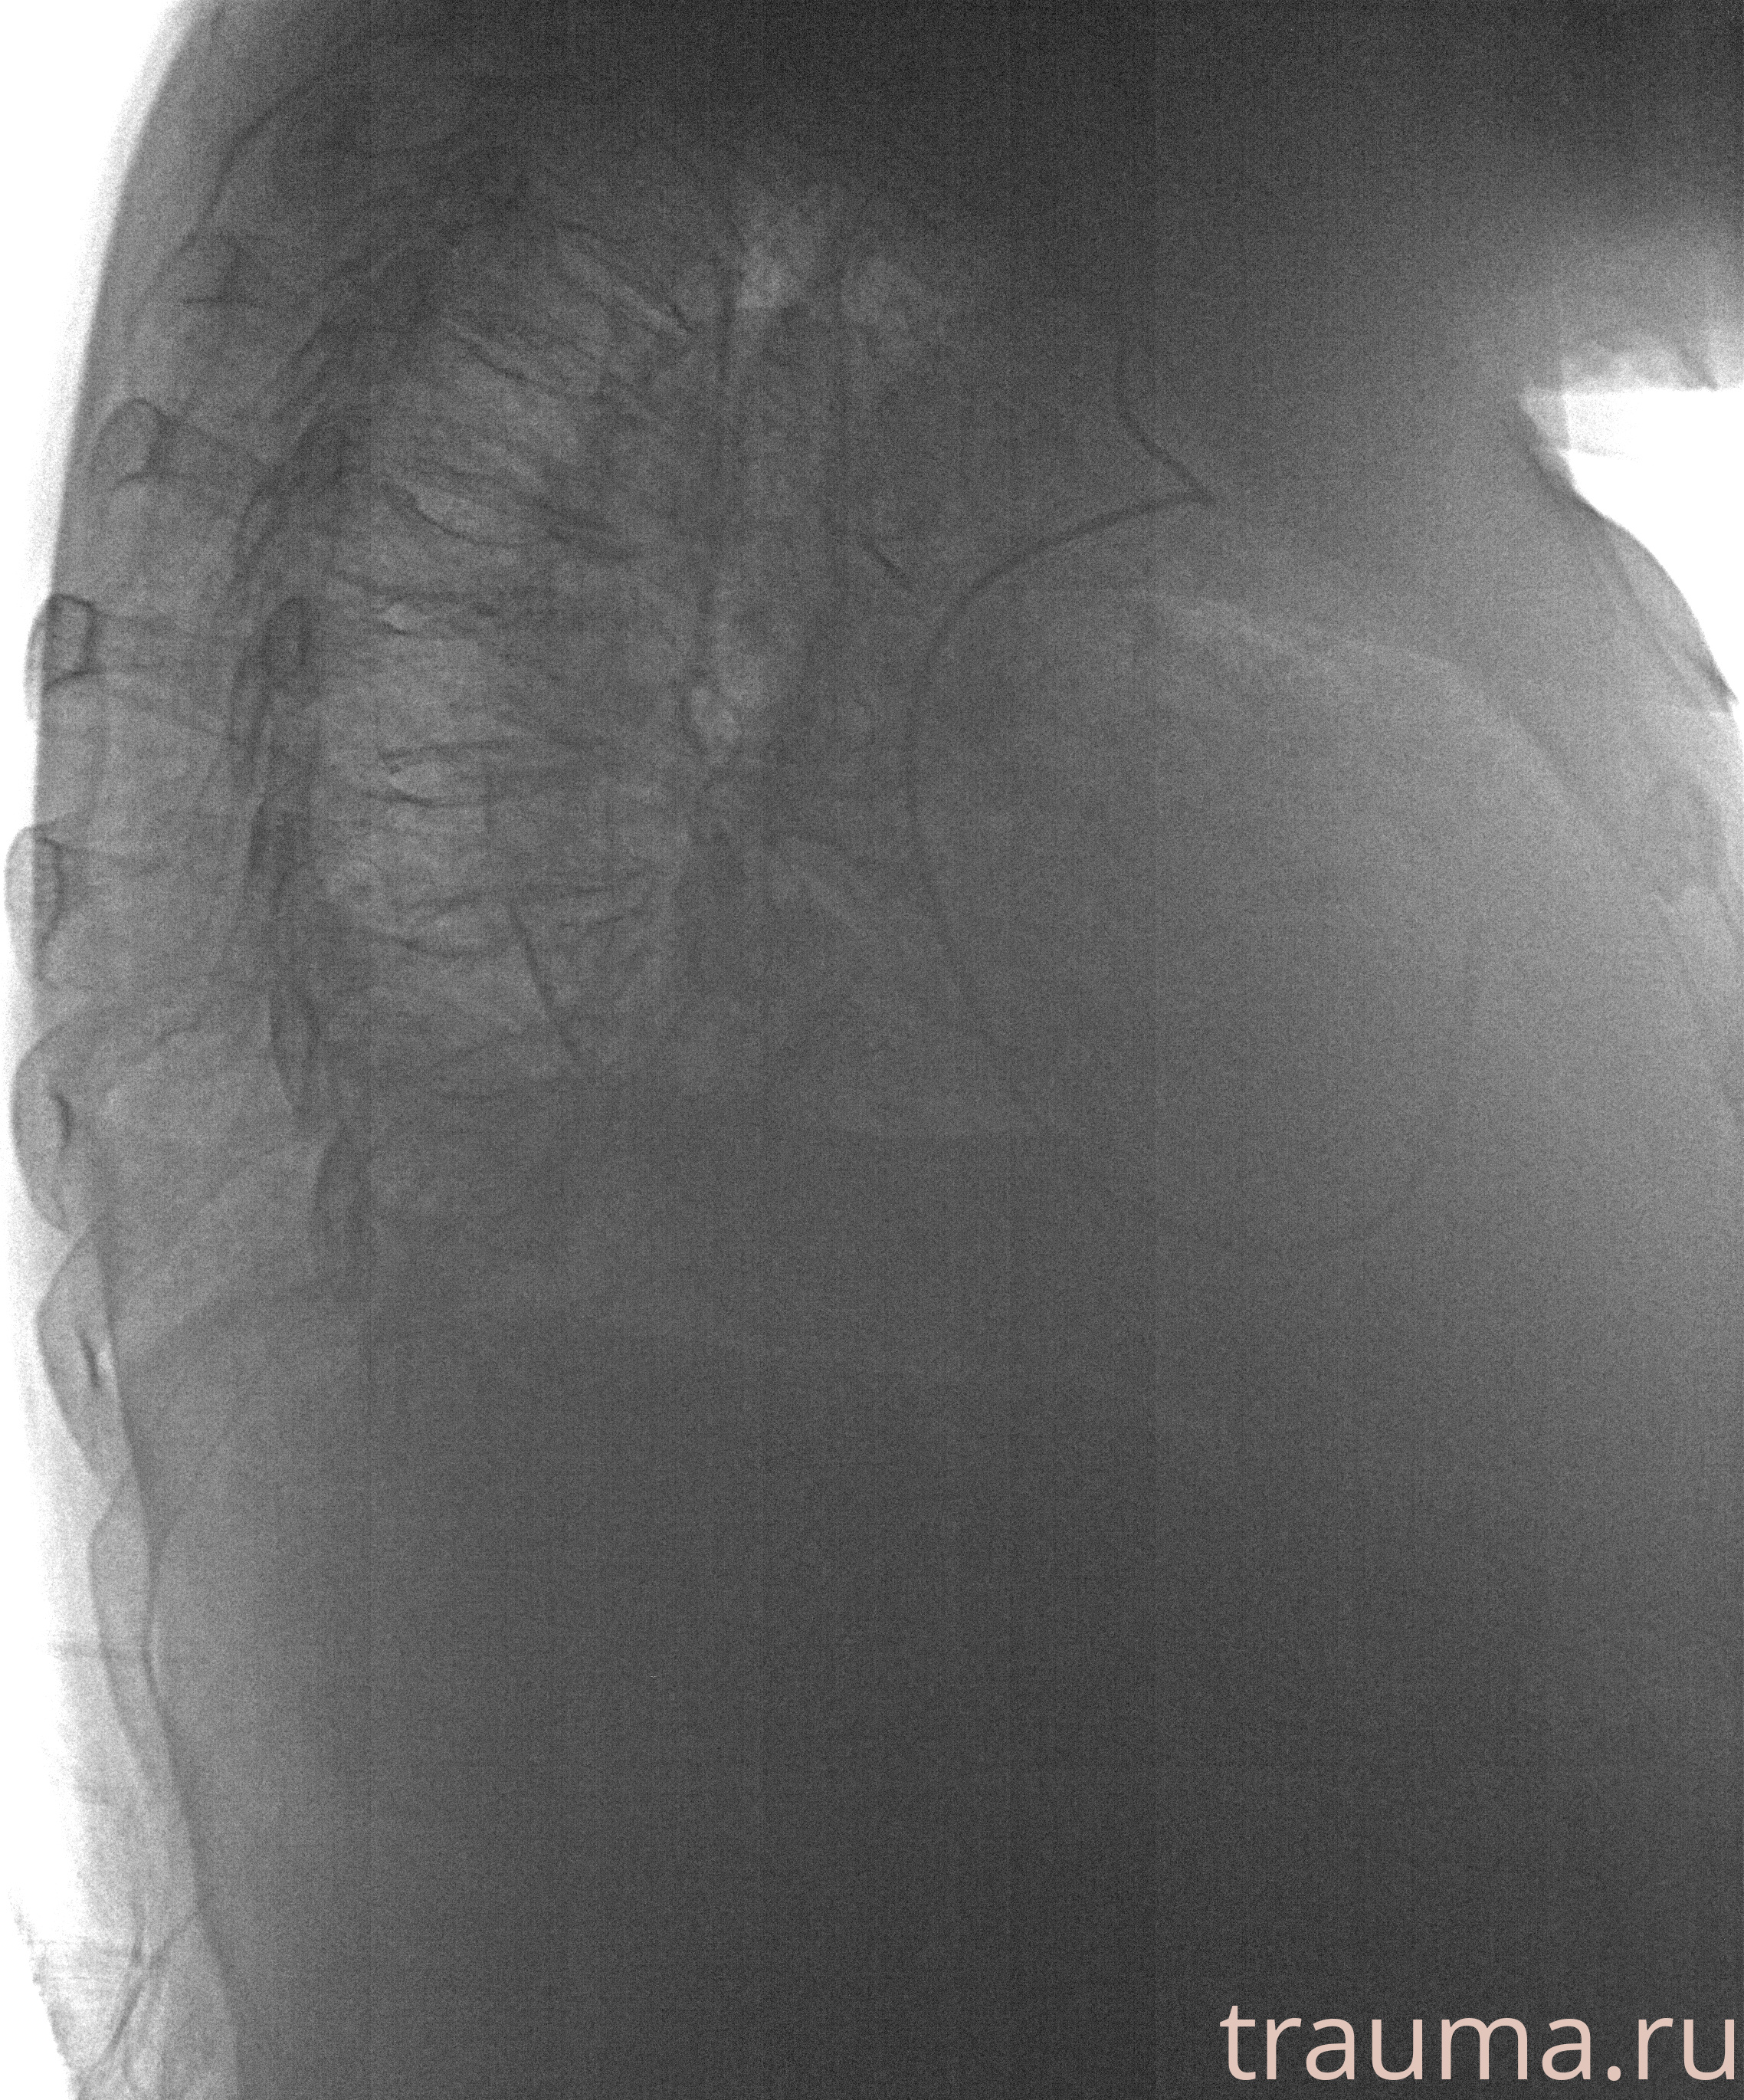

Рентгенограммы

Рентген на дому: по вашему адресу приезжает врач-рентгенолог, травматолог-ортопед с мобильным рентгеновским аппаратом, проводит диагностику травмы или заболевания, делает необходимые рентгенограммы, дает рекомендации по дальнейшему лечению. Получить качественные снимки в домашних условиях возможно благодаря уникальной методике, разработанной МосРентген Центром для института  Склифосовского

Яркость: 1   Контраст: 1   Инвертировать: 0 Увеличение: 1

Перетаскивайте мышь вверх/вниз для контраста, влево/право для яркости. Прокрутка колесом изменяет масштаб. Нажмите Сбросить для возврата к исходному изображению. При увеличении держите мышь в той области, которую хотите рассмотреть.